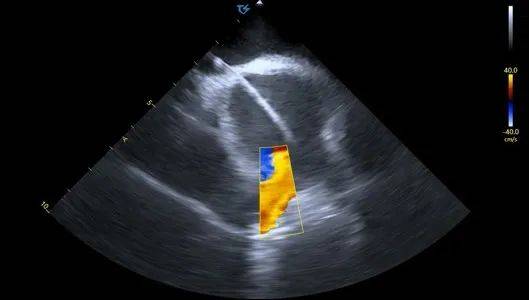

血流模式确认左上肺静脉

血流模式确认左下肺静脉